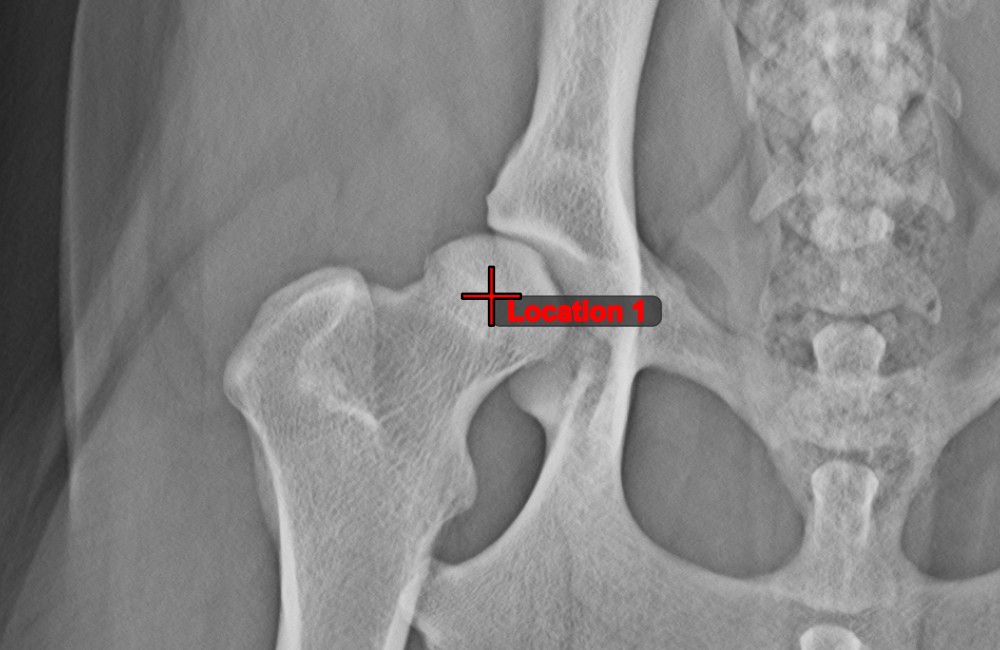

Label and comment important information on the image by using the Text Tool. The text is always assigned to a point that can be later modified by using the Select/Move Item tool.

• Select the tool from the left toolbar and assign it to one of the available mouse buttons.

• Mark the point on the scene where the new label will be added.

• Specify the text of the label and press OK to complete the measurement.